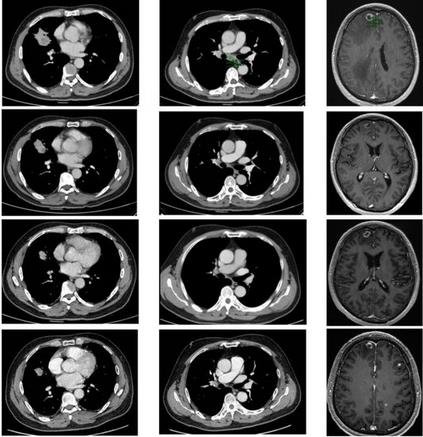

4.洛拉替尼/劳拉替尼(Lorlatinib)治疗肺癌脑转移有显著的效果

劳拉替尼在控制脑部病灶方面展现出了惊人的效果。其颅内客观缓解率高达82%,远超过对照组的23%。劳拉替尼治疗组的颅内完全缓解(CR)率更是高达71%,这充分体现了劳拉替尼的强大入脑能力。

“44岁冷先生在2020年被诊断为ALK阳性肺腺癌 cT2aN3M1b IV 期(脑转移)。在伽玛刀( γ 刀)治疗脑转移瘤后,开始克唑替尼一线治疗,250mg,每日两次,获得初始反应。但一年后虽然他的原发病灶仍然稳定,但由于脑结节的数量和大小的增加,他被评估为进展性疾病(PD)。随后接受培美曲塞(500 mg/㎡)、卡铂(AUC=4.25)联合贝伐珠单抗(15 mg/kg)治疗,共4个周期,之后用培美曲塞加贝伐珠单抗进行维持性治疗,共10个周期。在11个月后,他的脑部病变再次恶化。随后开始选择印度劳拉替尼(100mg,每日一次)作为后续治疗方案,治疗3个月,患者获得了非常明显的肿瘤缩小,脑转移瘤和脊髓肿瘤缩小,疗效评价PR。用药6个月以后,临床症状迅速好转,左腋窝淋巴结肿大明显缩小,疲劳和呼吸急促得到改善,病灶持续缩小,颅外病变仍保持稳定。至今,冷先生仍在持续接受治疗。”